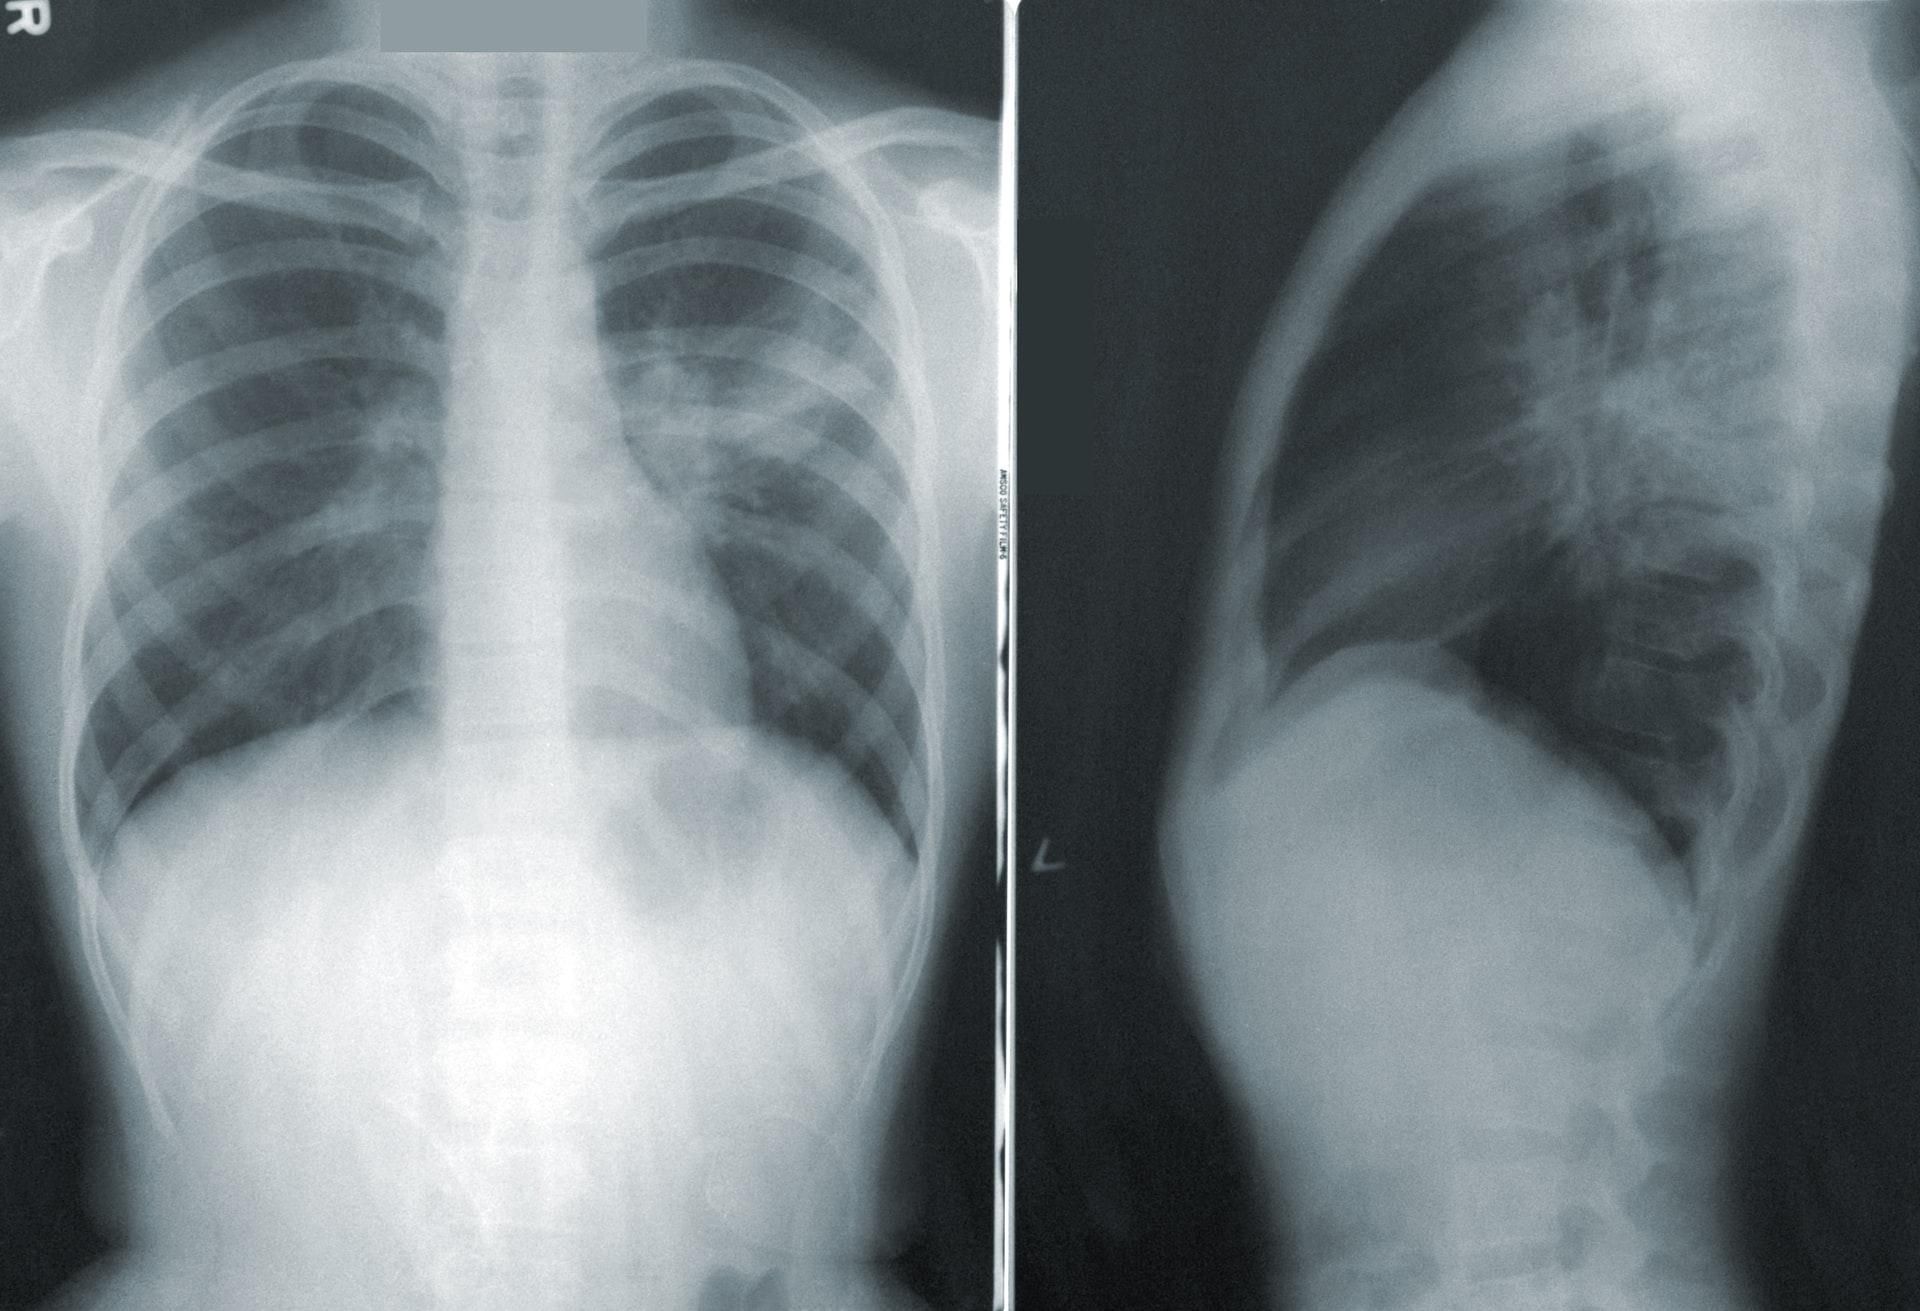

Однако обычные методы обследования (включая компьютерную и магнитно-резонансную томографии) часто не проявляют изменений в работе легких. Причины этих симптомов до сих пор во многом остаются загадкой.

В новом исследовании участвовали девять пациентов, страдающие от постковидного синдрома в течение не менее полугода после госпитализации. Компьютерная томография не выявила изменения в их легких, однако у них сохранились одышка и усталость.

Ученые провели им обследование с помощью новейшего метода – магнитно-резонансной томографии с использованием гиперполяризованого ксенона (МРТ 129Xe). Эта технология позволяет узнать ранее недоступные исследователям подробности о функции легких.

На изображениях, полученных при МРТ 129Xe, ученые обнаружили нарушения, невидимые для других методов. Во всех отделах легких девяти пациентов наблюдалось затруднение проникновения кислорода из альвеол в кровь. Новейшая технология подтверждает факт повреждения легких при длительном ковиде, данные полученные с ее помощью показывают, что это состояние – не просто ипохондрия.